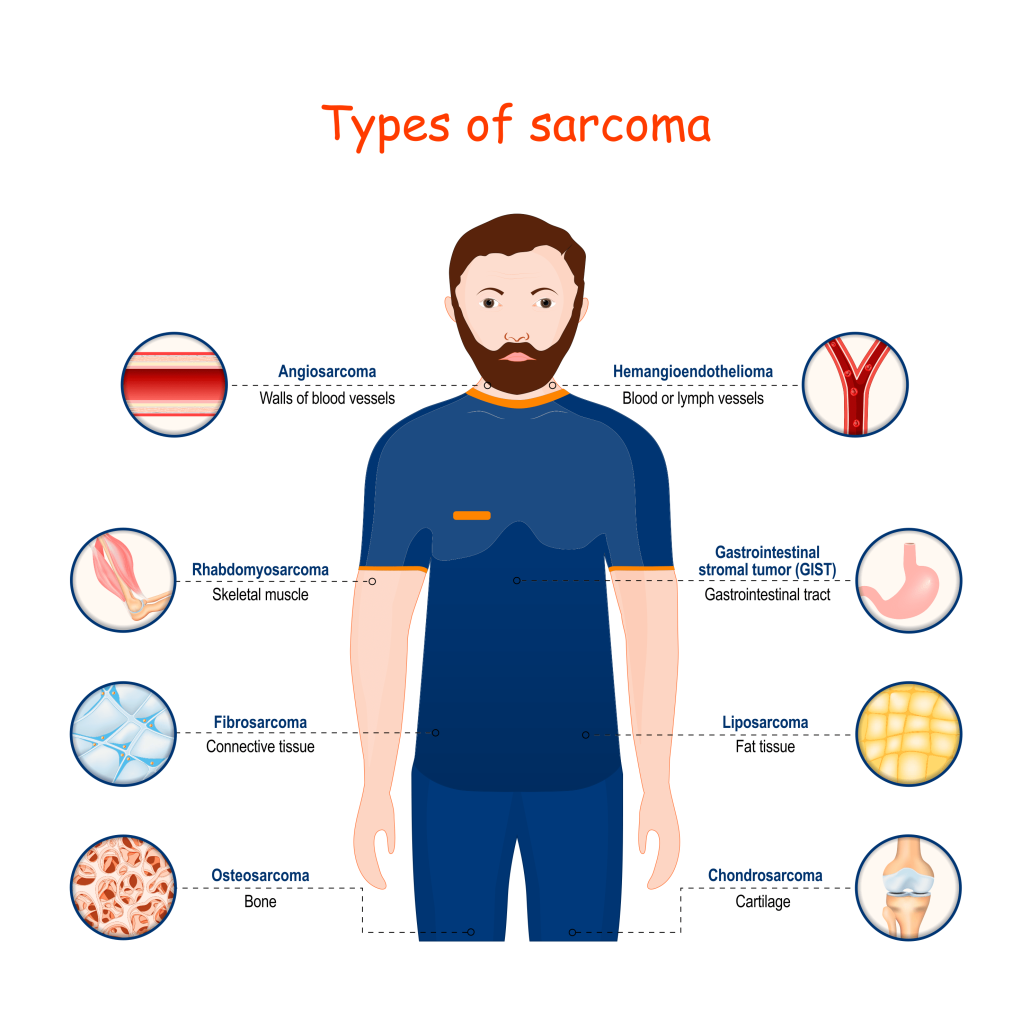

Soft Tissue Sarcoma Travocure

Soft Tissue Sarcoma Everything You Need To Know ACTC